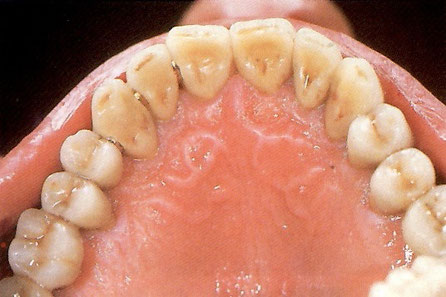

図24a 完成。口腔内装着状態の頬側面観。

図24b 完成。口腔内装着状態の咬合面観。